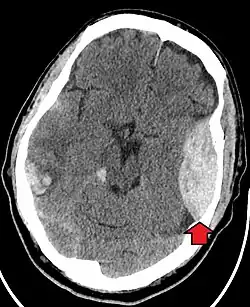

A principal preocupação clínica com o trauma contuso na cabeça é o dano ao cérebro, embora outras estruturas, como crânio, face, órbitas e pescoço, também possam estar em risco.[9] Após haver avaliação das vias aéreas, circulação e respiração, um colar cervical pode ser colocado no paciente se houver suspeita de trauma no pescoço. Em seguida, procede-se com levantamento secundário de evidências de que haja trauma craniano, como a presença de hematomas, contusões, lacerações e escoriações. Além de se observarem lesões externas, o exame neurológico completo é tipicamente realizado para que sejam avaliados danos ao cérebro. Dependendo do mecanismo da lesão e das avaliações, tomografia computadorizada do crânio e do cérebro pode ser realizada. Ela normalmente é feita para avaliar se há hemorragia intracraniano ou fratura dos ossos cranianos.[18]

Uma tomografia computadorizada mostrando um hematoma epidural, uma variedade de sangramento intracraniano comumente associada a trauma fechado na região temporal

A maioria dos pacientes com grave traumatismo cranioencefálico apresenta uma combinação de lesões intracranianas, podendo ser incluídas lesão axonal difusa, contusões cerebrais e hemorragias intracranianas, como hemorragia subaracnóidea, hematoma subdural, hematoma epidural e hemorragia intraparenquimatosa.[9][18] A recuperação da função cerebral após uma lesão traumática é altamente variável e depende das lesões intracranianas específicas existentes. Porém, existe uma significativa correlação entre gravidade da lesão inicial e nível de função neurológica durante a primeira avaliação e o nível de déficits neurológicos duradouros.[18] O tratamento inicial pode ser direcionado à redução da pressão intracraniana se houver preocupação com inchaço ou sangramento dentro do crânio, podendo exigir cirurgias como a hemicraniectomia, na qual parte do crânio é removida.[9][18]